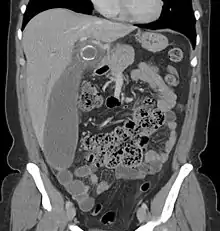

Computed tomography

Where it is readily available, computed tomography (CT) has become frequently used, especially in people whose diagnosis is not obvious on history and physical examination. Although some concerns about interpretation are identified, a 2019 Cochrane review found that sensitivity and specificity of CT for the diagnosis of acute appendicitis in adults was high.[59] Concerns about radiation tend to limit use of CT in pregnant women and children, especially with the increasingly widespread usage of MRI.[60][61]

The accurate diagnosis of appendicitis is multi-tiered, with the size of the appendix having the strongest positive predictive value, while indirect features can either increase or decrease sensitivity and specificity. A size of over 6 mm is both 95% sensitive and specific for appendicitis.[62]

However, because the appendix can be filled with fecal material, causing intraluminal distention, this criterion has shown limited utility in more recent meta-analyses.[63] This is as opposed to ultrasound, in which the wall of the appendix can be more easily distinguished from intraluminal feces. In such scenarios, ancillary features such as increased wall enhancement as compared to adjacent bowel and inflammation of the surrounding fat, or fat stranding, can be supportive of the diagnosis. However, their absence does not preclude it. In severe cases with perforation, an adjacent phlegmon or abscess can be seen. Dense fluid layering in the pelvis can also result, related to either pus or enteric spillage. When patients are thin or younger, the relative absence of fat can make the appendix and surrounding fat stranding difficult to see.[63]